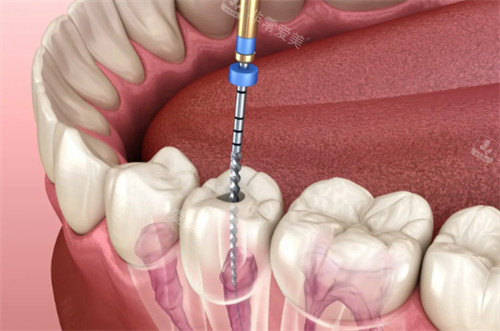

正在进行根管治疗的牙齿

治疗难度也直接影响收费,比如根管存在钙化堵塞、弯曲变异等情况,医生需要额外花费时间疏通、塑形,甚至用到特殊器械,费用会比常规病例高出20%-40%。

治疗技术与材料的选择同样关键,采用热牙胶充填技术的治疗,因封闭性更好、长期成效更稳定,比传统牙胶尖充填贵100-300元/颗。而进口消毒材料、生物相容性充填剂的使用,也会让整体费用有所提升。